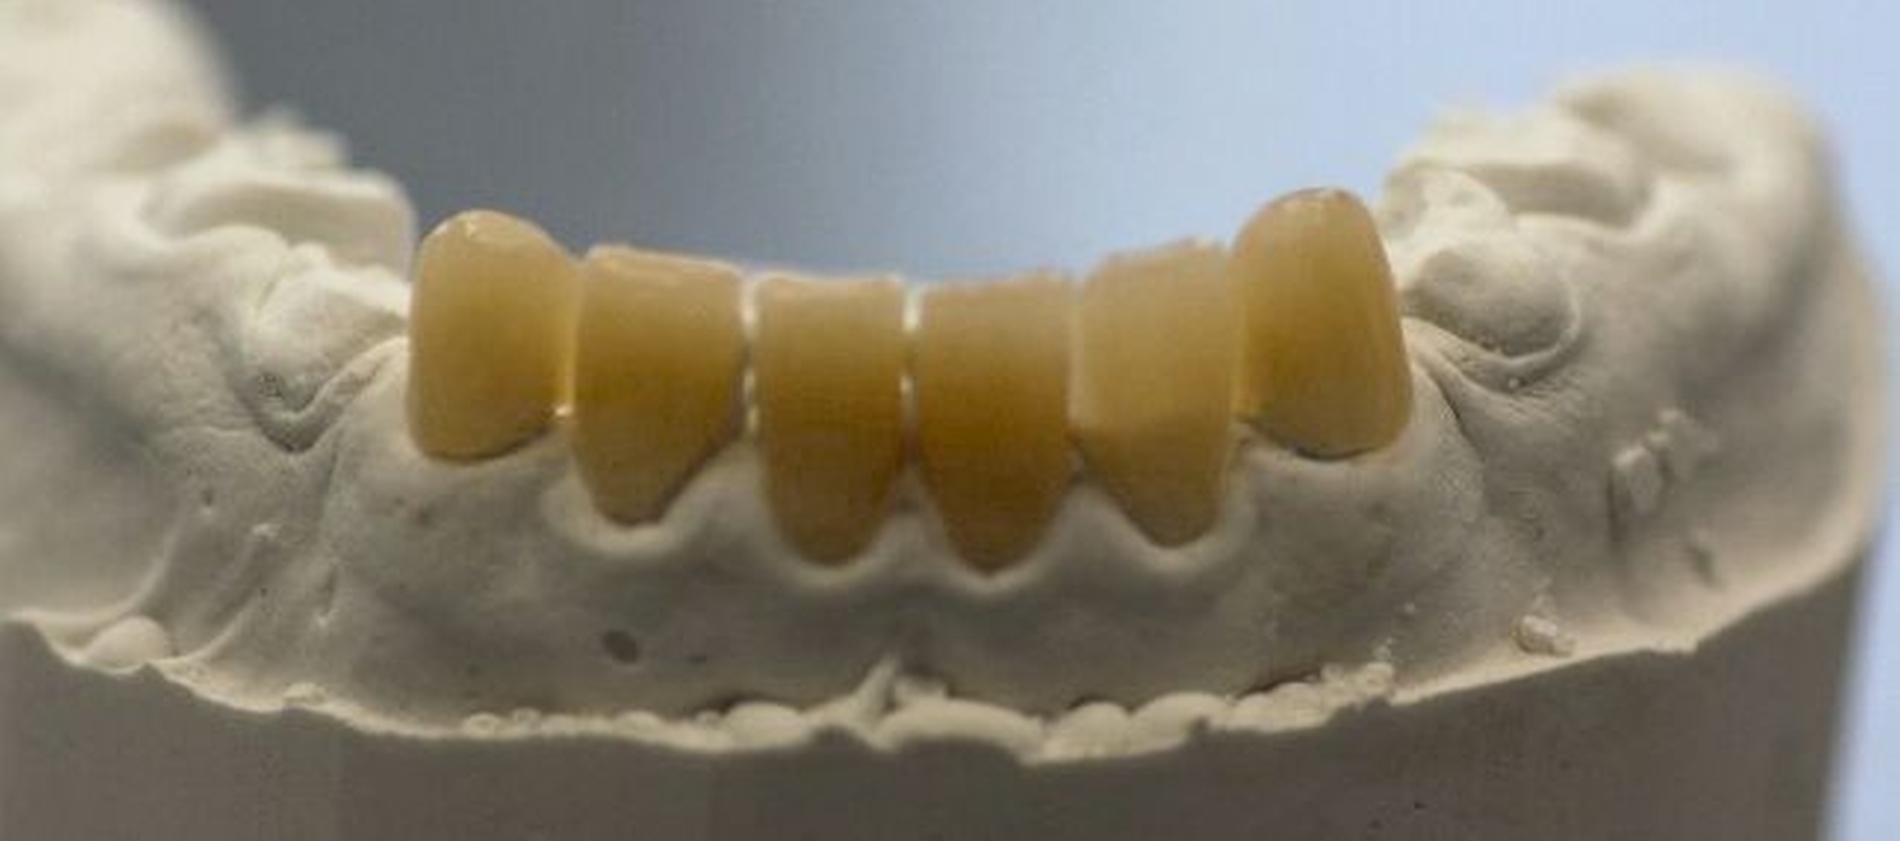

Nach der Extraktion von Zahn 64 wurden die übrigen kariösen Milchzähne nach Konditionierung (Prime&Bond NT, Dentsply Sirona) mit Kompomer (Dyract extra, Dentsply Sirona) versorgt. Für die Frontzahnbehandlung wurde zunächst ein Wax-up auf Situationsmodellen erstellt (Abbildung 3), anschließend eine Silikonformhilfe angefertigt. Nach Reinigung und 3-Schritt-Etch-and-Rinse-Konditionierung (OptiBond FL, Kerr) unter relativer Trockenlegung wurden die Zähne in Mehrschichttechnik mit einem Mikrohybrid-Komposit (Herculite XRV, Kerr) versorgt. Die Seitenzähne wurden wegen des ausgeprägten Würgereizes unter absoluter Trockenlegung mit fließfähigem Komposit (Tetric flow, Ivoclar Vivadent) temporär rekonstruiert (Abbildung 4).